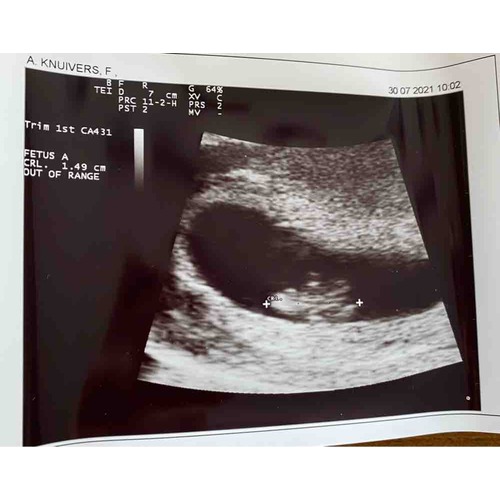

Een verse echo van vanochtend :) 8w5d